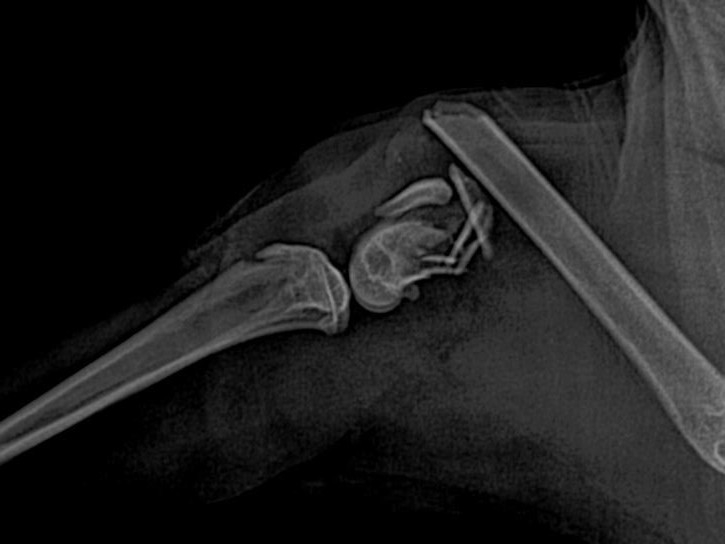

(사진을 보여주며) 이게 엑스레이 사진 이거든요

의사

고양이 뒷다리 부분인데

한눈에 봐도 많이 골절됐죠?

다행히 크게 다친건 뒷다리 뿐이고

다른곳은 조금 금이 가거나

아니면 약한 탈골정도라서

일단은 안심하셔도 될것 같습니다

우선 입원을 몇달간 해야될것같아요

다리 골절 수술도 해야되고

탈수랑 영양실조도 조금 있어서

그것도 치료를 좀 해야될것 같아요